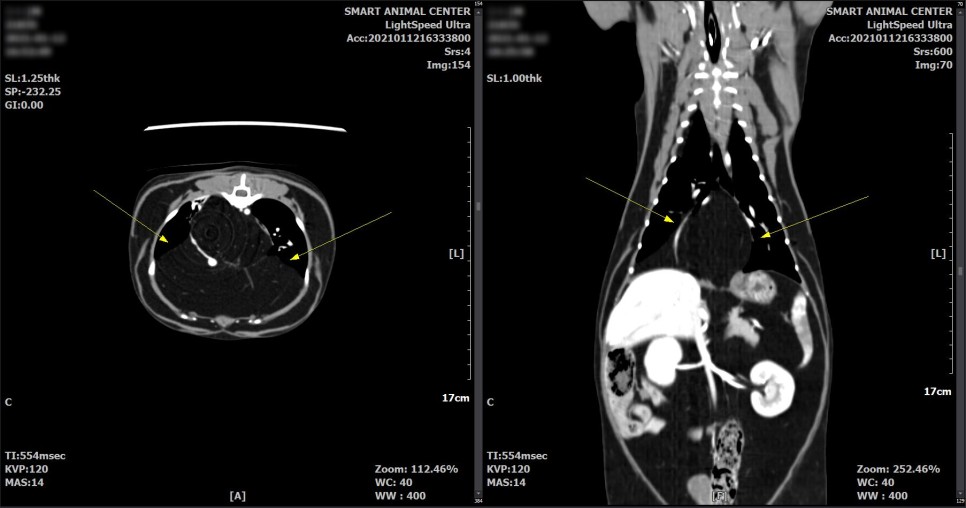

보다 면밀한 흉부 평가를 위해서 CT촬영을 실시했습니다.

CT 검사 결과

횡격막의 일부 결손 부위와 흉강 내 다량의 지방 병변이 확인되었습니다.

횡격막 결손부에 의한 다량의 지방 디스크가 있을 수 있으며,

또한 영상학적으로 악성도를 지시하는 것과 같은 소견은 관찰되지 않았습니다.

다량의 지방으로 폐 실질 등, 왼쪽 변위가 유발되고 있다고 판단되었습니다.